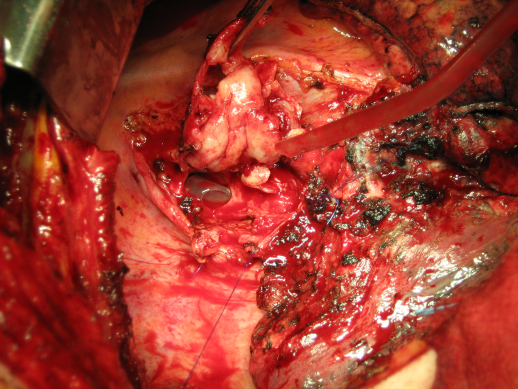

Bei einer tief greifenden Infektion, symptomatisch durch Brustschmerzen, Fieber, Sternuminstabilität oder eitriges Drainagesekret ist eine rasche operative Revision nötig (Abbildung 15 [Abb. 15]). Bei Nachweis von Knochennekrosen (Ostoemyelitis) ist ein „offenes“ Verfahren zu wählen, um die Infektion zu kontrollieren und eine Mediastinitis abzuwenden. Die Curretage (Abbildung 16 [Abb. 16]) der Nekrosen bzw. Knochensequester ist dabei essentiell, ebenso die Entfernung der Drahtcerclagen. Durch Methylenblauinstillation lassen sich Fistelgänge darstellen, die sorgfältig abgetragen werden müssen (Abbildung 17 [Abb. 17]). Durch regelmäßige Tamponadenbehandlung mit aseptischen Lösungen kann die Wunde durch sekundäre Granulation zur Ausheilung gebracht werden. Diese Methode ist aber sehr zeitaufwendig. Bei nicht beherrschbaren Nekrosen muss ggf. als Ultima ratio-Maßnahme die partielle oder sogar totale Sternektomie erwogen werden.

Abbildung 15: Sternuminfektion

Abbildung 16: Sternumcurretage

Abbildung 17: Nekrosektomie nach Fisteldarstellung mit Methylenblau